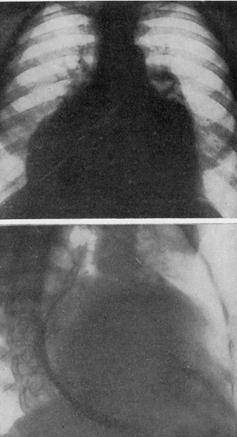

РЕНТГЕНОГРАММЫ БОЛЬНОГО С НЕДОСТАТОЧНОСТЬЮ АОРТАЛЬНЫХ КЛАПАНОВ.

Типичная аортальная конфигурация сердца. Локальное увеличение левого желудочка. Расширение аорты. На рентгенокимограмме — возбужденная пульсация по дуге левого желудочка. На аорте — зубцы по амплитуде значительно превышают желудочковые.